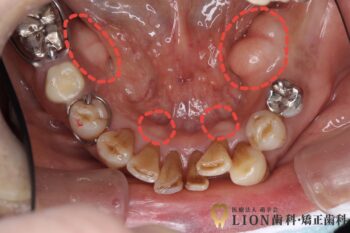

こちらは下顎の骨隆起の症例写真です。赤丸の箇所が骨隆起です。